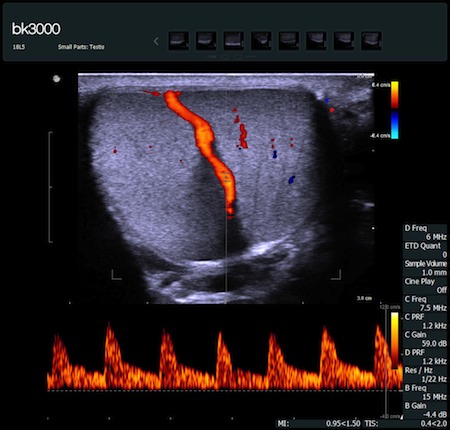

Fot. Tętnica jądrowa - obraz uzyskany głowicą 18L5 - opcja PW Doppler.